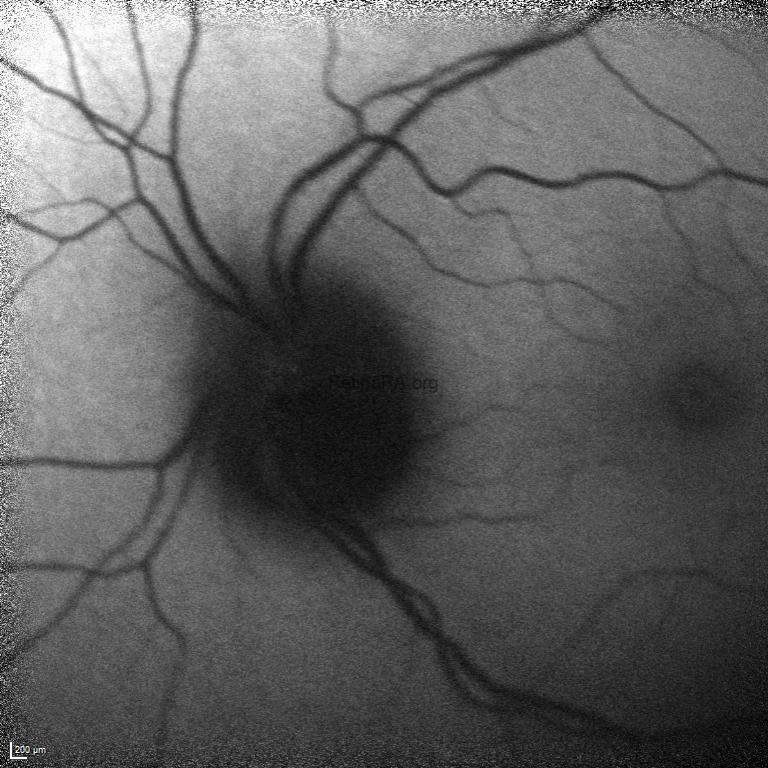

Fundus autofluoresce demonstrated hypo-autofluorescence corresponding to the pigmented mass on the optic disk.